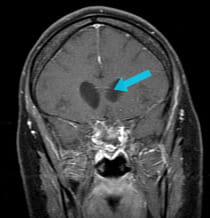

A 35-year-old woman was experiencing headache and vision loss from pressure and swelling in her brain related to a large tumor at the base of her skull. The tumor was an olfactory groove meningioma.

pre-surgical scan of large olfactory groove meningioma

Pre-surgical scan shows a large olfactory groove meningioma.